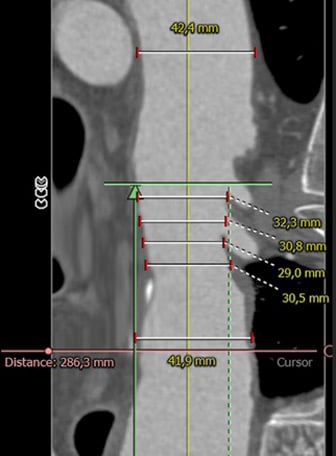

Distal Arch / Proximal descending

Length & extent

Distal landing zone

- Further extension of the 37 x 200 mm Gore® TAG® Conformable with a large diameter tapered 37/31 x 150 mm TAG® Conformable

- Adaptation to the patient’s individual anatomy by extending the 37 mm TBE with an additional 37 mm TAG® Conformable with long overlap.

- Further extension of the 37 mm TAG® Conformable with Large Diameter Tapered TAG® Conformable to match the distal aortic diameter.